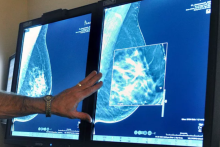

الگوریتم‌های هوش مصنوعی در شناسایی سرطان سینه از طریق تصاویر رادیولوژی آن‌قدر دقیق هستند که در برخی موارد حتی عملکردی بهتر از پزشکان دارند.

به گزارش سیتنا به تقل از دویچه وله، در حال حاضر، سازمان خدمات سلامت بریتانیا (NHS) از هوش مصنوعی برای تحلیل ماموگرافی‌ها استفاده می‌کند تا مواردی از سرطان را که ممکن است از چشم پزشکان پنهان بمانند، تشخیص دهد.

روش‌های سنتی تشخیص سرطان معمولاً بر تشخیص نشانه‌های مستقیم تومورهای سرطانی متمرکز هستند. برای مثال، در ماموگرافی تغییراتی در بافت پستان مشاهده می‌شود که می‌تواند نشان‌دهنده‌ سرطان، حتی پیش از بروز علائم بالینی باشد. همچنین، در بیوپسی (نمونه‌برداری از بافت)، پزشکان به دنبال نشانه‌های مولکولی سرطان در سلول‌های بدن هستند.